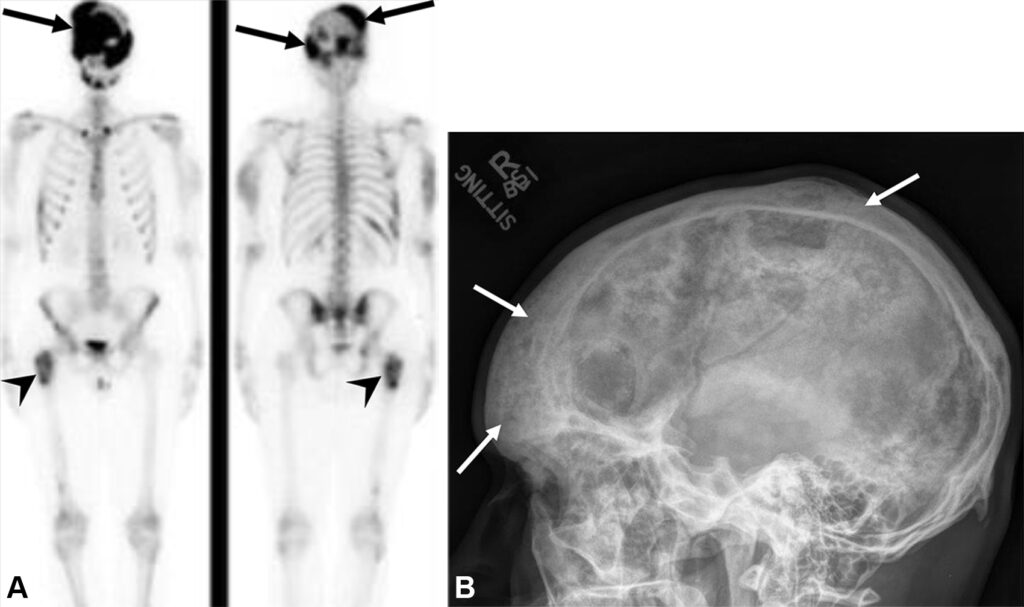

Sindrome di McCune-Albright (MAS) in un uomo di 32 anni con ingrossamento della volta cranica e macchie caffellatte.

L’esame total body evidenzia un’ipercaptazione multifocale del tracciante, di intensità variabile, in corrispondenza di aree ossee espanse (in questo caso localizzate prevalentemente a livello del cranio e del femore prossimale destro).

L’RX laterale del cranio conferma l’alterazione strutturale delle aree ipercaptanti craniche, mostrando il tipico aspetto “a vetro smerigliato” (ground-glass), che rappresenta il segno radiologico distintivo della displasia fibrosa.

La sindrome di McCune-Albright è una rara patologia genetica definita dalla presenza di una classica triade clinica: displasia fibrosa (spesso nella forma poliostotica, che coinvolge più segmenti ossei), iperpigmentazione cutanea (macchie caffellatte) ed endocrinopatie iperfunzionanti (storicamente pubertà precoce, ma anche ipertiroidismo o eccesso di ormone della crescita).